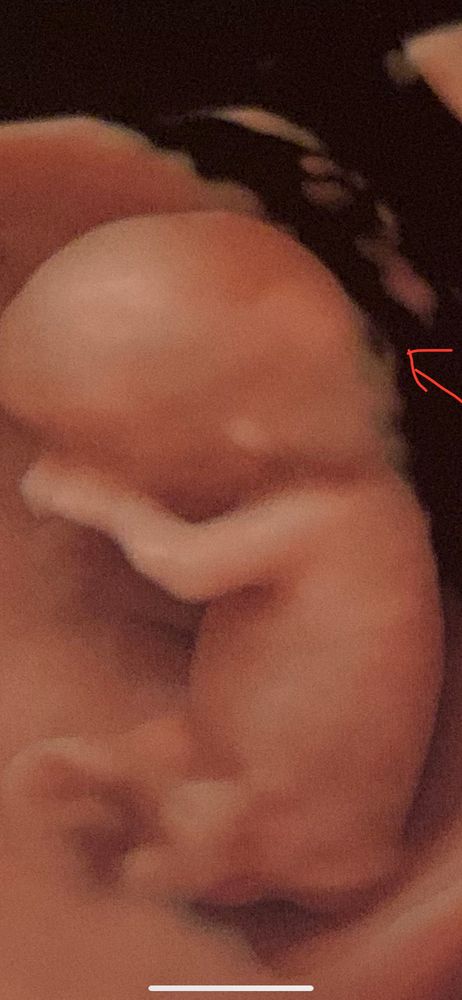

ff

Вот мой снимок. Что шеи нет у ребенка? А что между подбородком и грудью острое? Может вытекло из него что то? А почему нос такой короткий? Даун? А где руки? Аплазия?

Вот вы так же смотрите

Эти все снимки с такими артефактами.. точность всегда не 100%. это как тест Роршаха. Будете долго смотреть найдёте что угодно что придет в голову. Не смотрите эти снимки